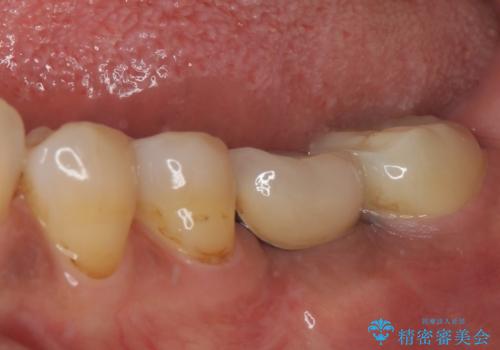

- 銀歯の装着されている奥歯がしみるとのことで来院された患者様です。

銀歯周辺の歯が欠けており、むし歯も進行している状態であったので、オールセラミッククラウンにて補綴治療を行うこととしました。

仮歯に変えた時点でしみる症状はなくなり、オールセラミッククラウンはまるで自分自身の歯のような舌触りとなり、大変満足していただきました。